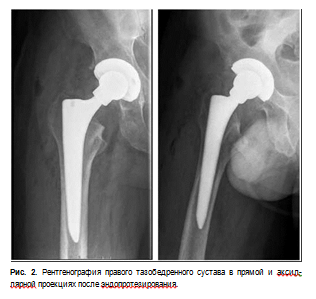

04.10.2023 выполнено оперативное лечение — тотальное эндопротезирование правого тазобедренного сустава имплантатом Aesculap TRJ.

Через сутки после оперативного лечения выполнен рентген правого тазобедренного сустава (рис. 2). Состояние всех компонентов эндопротеза удовлетворительное.